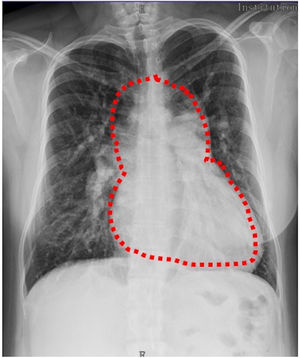

En nuestro caso presentamos a una paciente de 30 años, sin intervenciones previas, con antecedentes de acropaquias desde los 6 años, sin otro síntoma. Fue derivada a nuestra institución con historia de disnea de medianos esfuerzos, palpitaciones, dolor torácico y deterioro de la clase funcional de 2 meses de evolución. En la radiografía de tórax se observó flujo pulmonar aumentado y cardiomegalia a expensas de las cavidades derechas, imagen en «muñeco de nieve» (fig. 1). En el ecocardiograma se evidenció conexión anómala total de venas pulmonares variedad supracardíaca a través de una vena vertical sin obstrucción, comunicación interauricular tipo ostium secundum, dilatación de cavidades derechas y presión sistémica estimada de la arteria pulmonar de 69mmHg. Se complementaron los estudios con tomografía computarizada por sospecha de tromboembolismo pulmonar, donde se encontró drenaje anómalo de todas las venas pulmonares derechas, las del lóbulo inferior y lingulares izquierdas, las cuales confluyen en un colector común horizontal, las venas pulmonares del lóbulo superior izquierdo confluyen en la unión del colector horizontal y longitudinal. Posteriormente, por medio del colector longitudinal izquierdo drenan a la vena innominada, y esta en la cava superior, desembocando en la aurícula derecha (fig. 2). Se descartó tromboembolismo pulmonar y trombosis venosa profunda en las extremidades inferiores. Se sometió a cateterismo cardiaco por vía femoral derecha, donde se determinó salto oximétrico en la vena cava superior y desaturación sistémica con relación a la vena pulmonar (aorta-PaO2: 53mmHg, SaO2 90% vs. vena pulmonar-PaO2: 87mmHg, SaO2 98%). En levofase el retorno venoso pulmonar derecho e izquierdo va hacia un colector, que desemboca en la vena vertical-innominada y posteriormente desemboca en la vena cava superior, con opacificación del atrio derecho y paso de medio de contraste al atrio izquierdo (AI) a través de un defecto septal auricular (fig. 3).